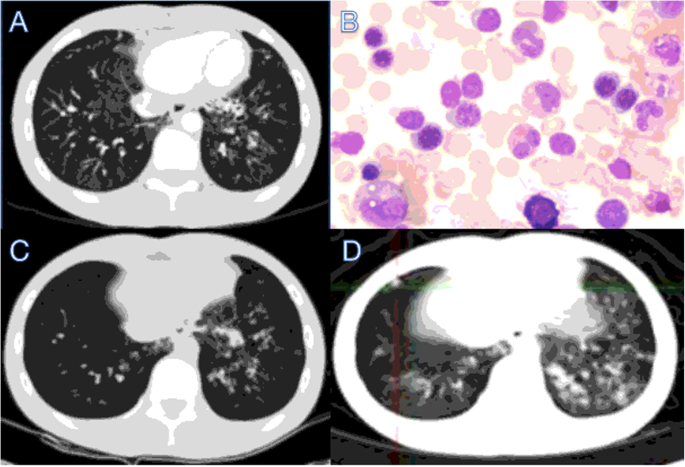

This case report was approved by Wuhan University Zhongnan Hospital. The 17-year-old patient has been slower than his peers in development and repeatedly experienced pulmonary bacterial infections and aphthous stomatitis since childhood. He became infected with varicella-zoster virus (VZV) and developed lung abscess when he was 10 years old. He was diagnosed with bronchiectasis and elevation of IgA (6.43 g/L) for the first time at the age of 15 years (Fig. 1a). The patient was treated with antiviral and antibiotics treatments discontinuous, and the treatments were interrupted when the symptoms were relieved. At the age of 17, he was 160 cm tall and weighed 40 kg, which was significantly shorter than a male of the same age. He revisited our hospital due to repeated coughing and the symptoms progressed with the treatment of oral antibiotics at home.

Severe bronchiectasis and bone marrow puncture in the 17-year-old male patient. a Bilateral bronchiectasis and bronchiolitis on chest computed tomography scan in the 16-year-old. b Cell morphous was observed by microscope of bone marrow puncture. c Bilateral bronchiectasis and bronchiolitis on chest computed tomography scan in the 17-year-old. d Bilateral bronchiectasis and bronchiolitis on chest PETCT

Further tests were conducted to determine the underlying pathogenesis, including quantitative serum immunoglobulin immunofixation electrophoresis and autoimmune disease-related antibody assays. We found no abnormality when detecting antibodies related to autoimmune diseases, with no abnormal bands by immunofixation electrophoresis. Therefore, we can rule out the common autoimmune diseases such as rheumatism, systemic lupus erythematosus and Sjogren’s syndrome. Levels of serum IgG (11.70 g/L) and IgM (1.00 g/L) were normal, but those of IgA (6.91 g/L) were elevated. We performed a bone marrow aspiration examination to rule out blood system diseases (Fig. 1b). The patient had repeated coughing; he was diagnosed with bronchiectasis many years ago, but the aetiology was not determined. Therefore, we reperformed chest CT, and the results indicated bronchiectasis (Fig. 1c), which was consistent with his previous diagnosis. At the same time, we performed whole-body positron emission tomography (PET) CT. Despite the presence of bronchiectasis, there were no signs of malignancy (Fig. 1d).